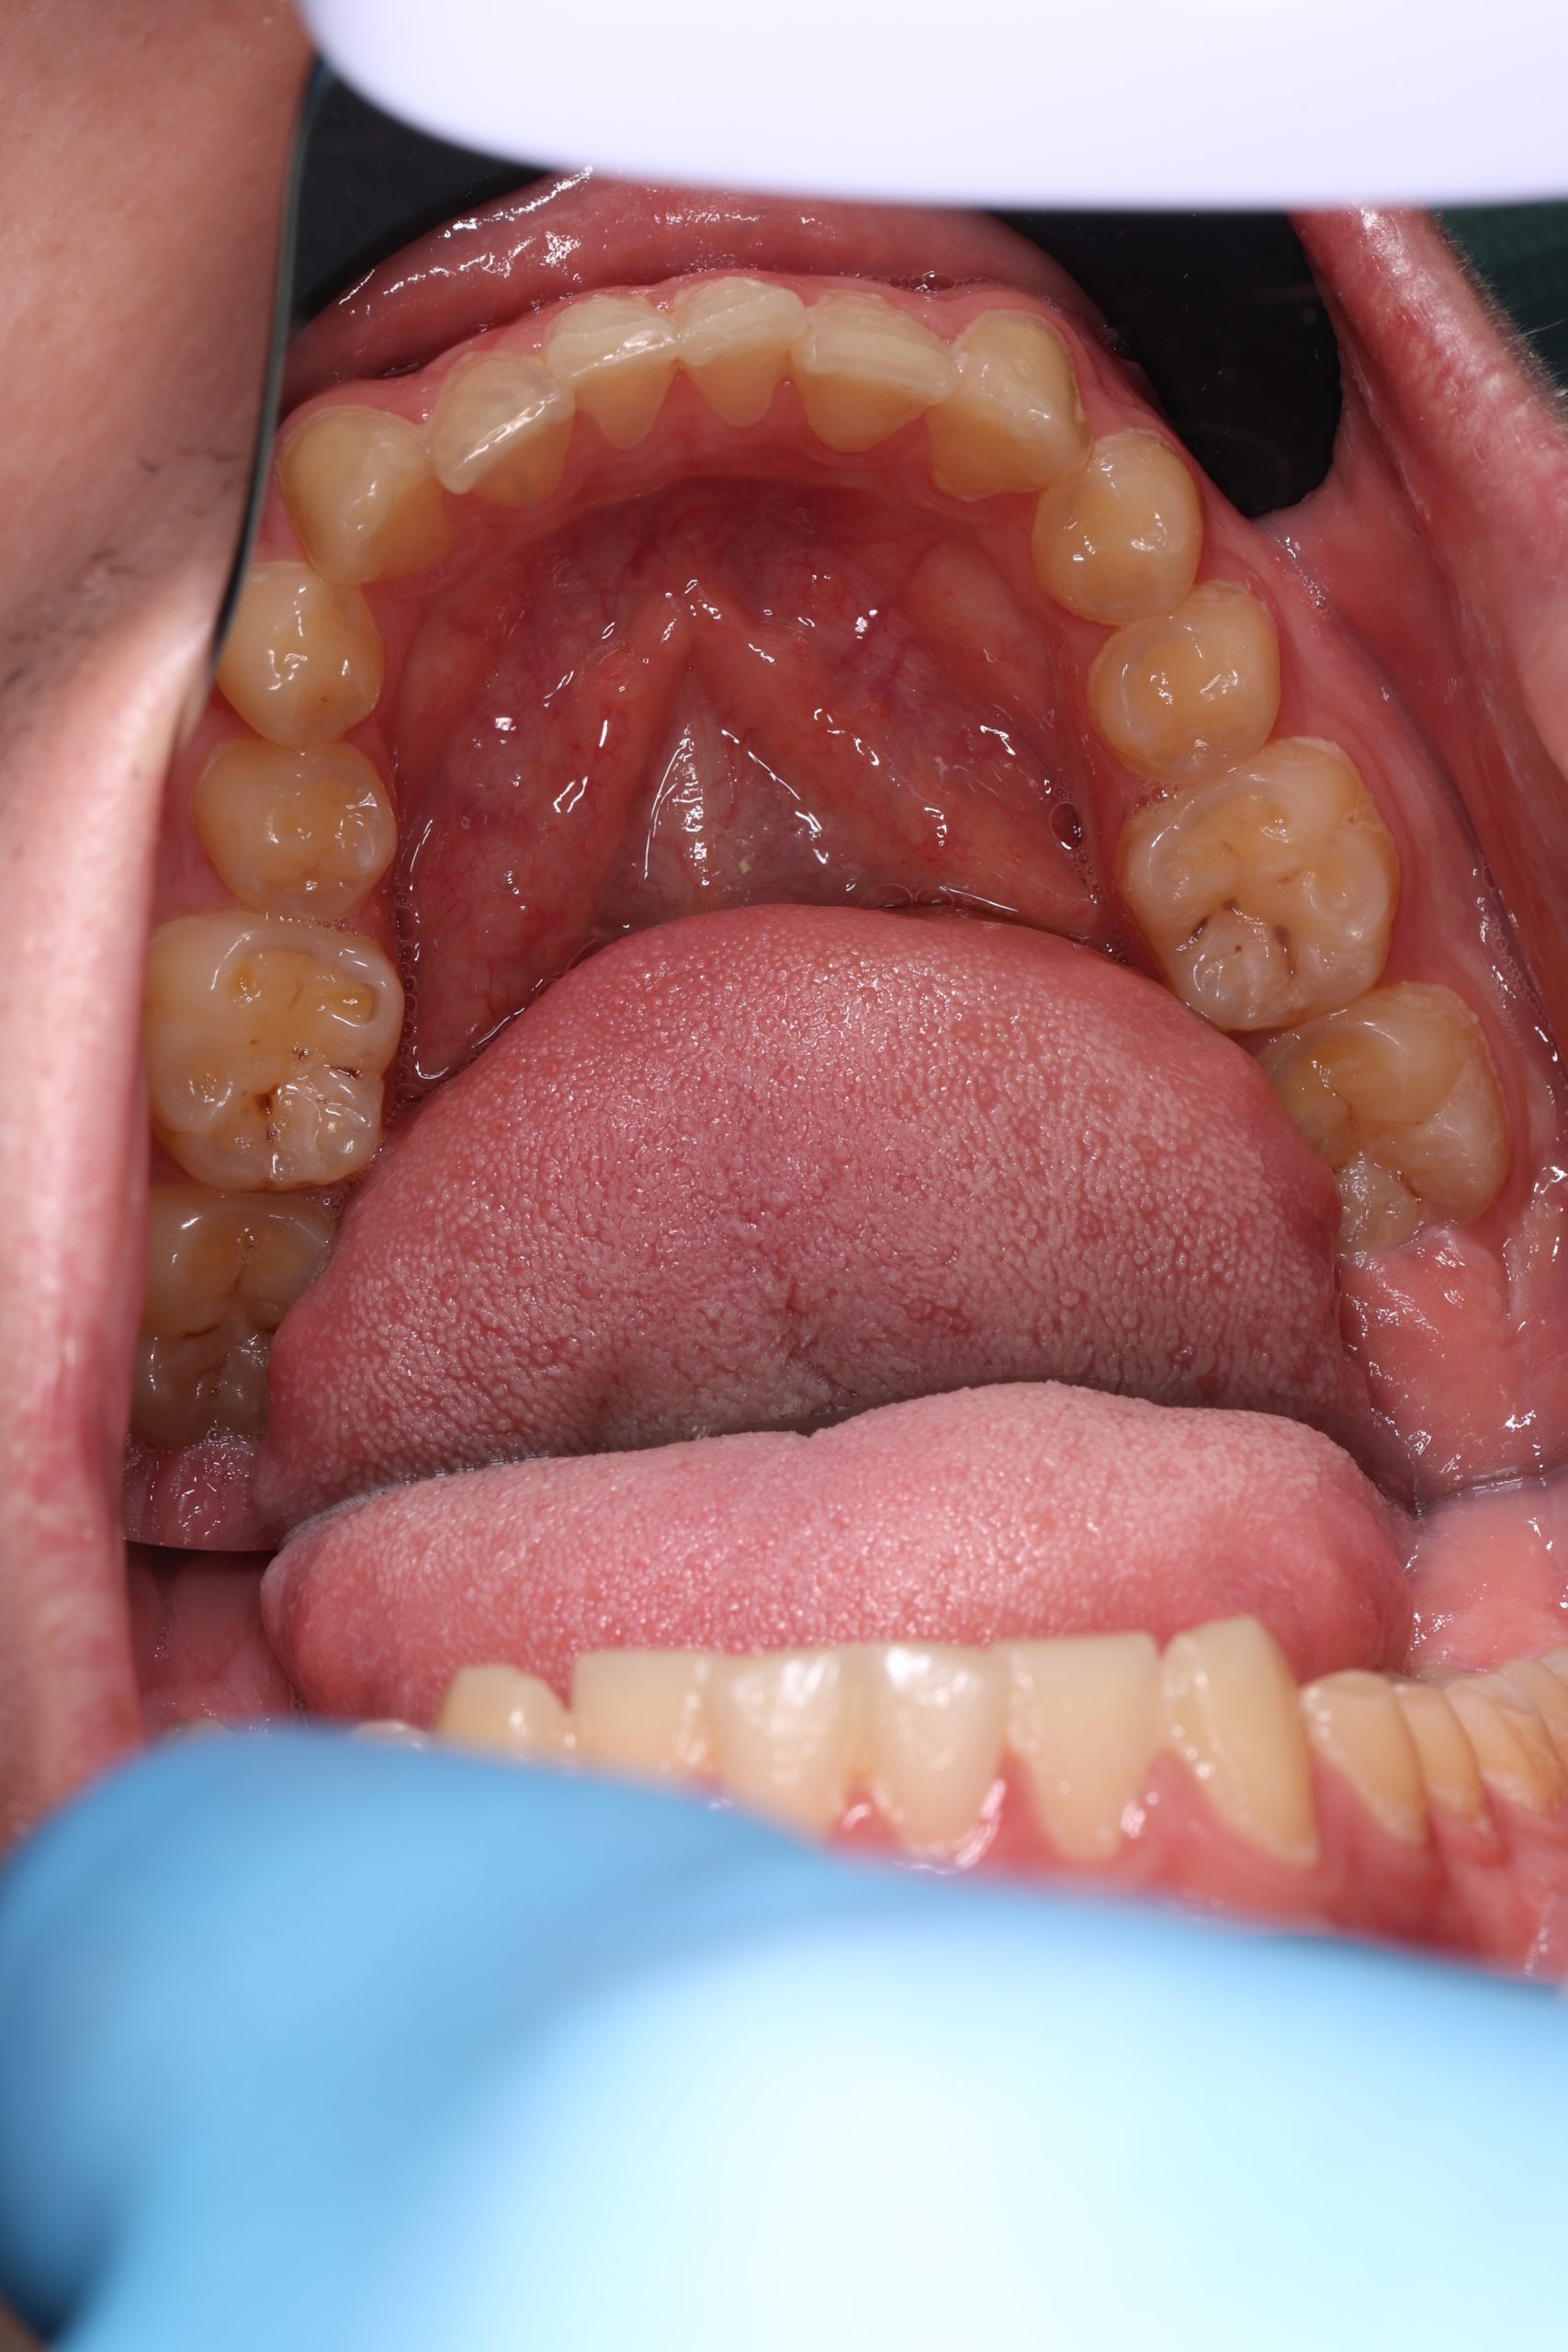

Inside every tooth lies a narrow chamber that contains nerves and blood vessels — the dental pulp. When deep decay, a leaking filling, or trauma allows bacteria to reach this inner space, the pulp becomes inflamed and then infected. The result is pressure, sensitivity, and often an unmistakable throbbing pain.

Under bright magnified light, a tiny opening is created and every canal located — even the hidden ones that often cause failures elsewhere. - Cleaning and shaping